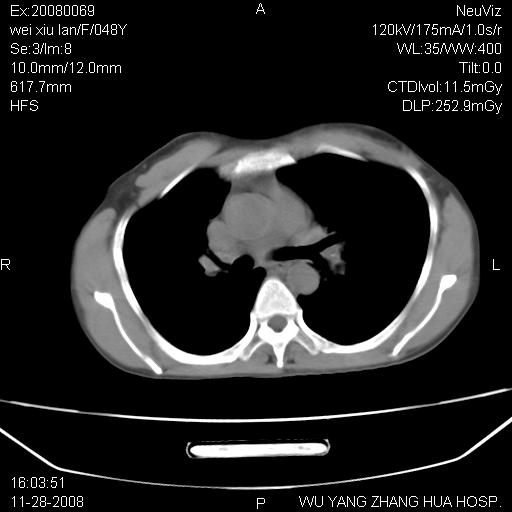

标题: CT16847:女,48岁,咳嗽,发热两日,平常偶有上腹部不适。 [打印本页]

标题: CT16847:女,48岁,咳嗽,发热两日,平常偶有上腹部不适。

能否考虑食管裂孔疝?请老师们多多指教。

这个是左侧膈膨升伴不完全性胃翻转,手术将松弛的左横膈膜折叠缝合即解决问题。

支持左侧膈疝,心脏受压右移.

左下肺不张、膈膨升,胸腔胃

胃、脾脏及部分肠管明显升高,并压迫心脏移位,

首先考虑:左侧膈疝。

左侧胸腔内见胃肠及脾脏影

支持膈疝

左膈顶及肋膈角均上移,膈面光滑,考虑左膈肌麻痹